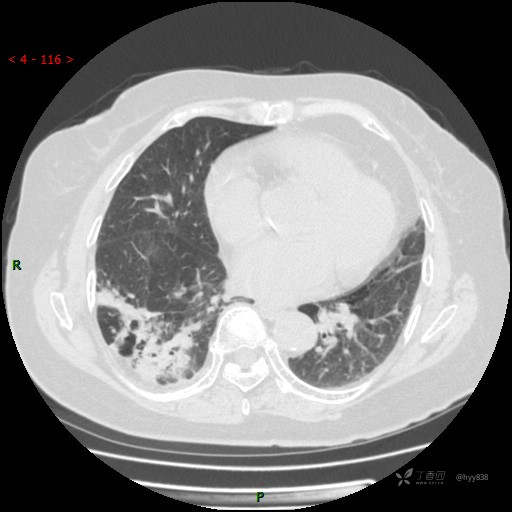

胸部CT平扫